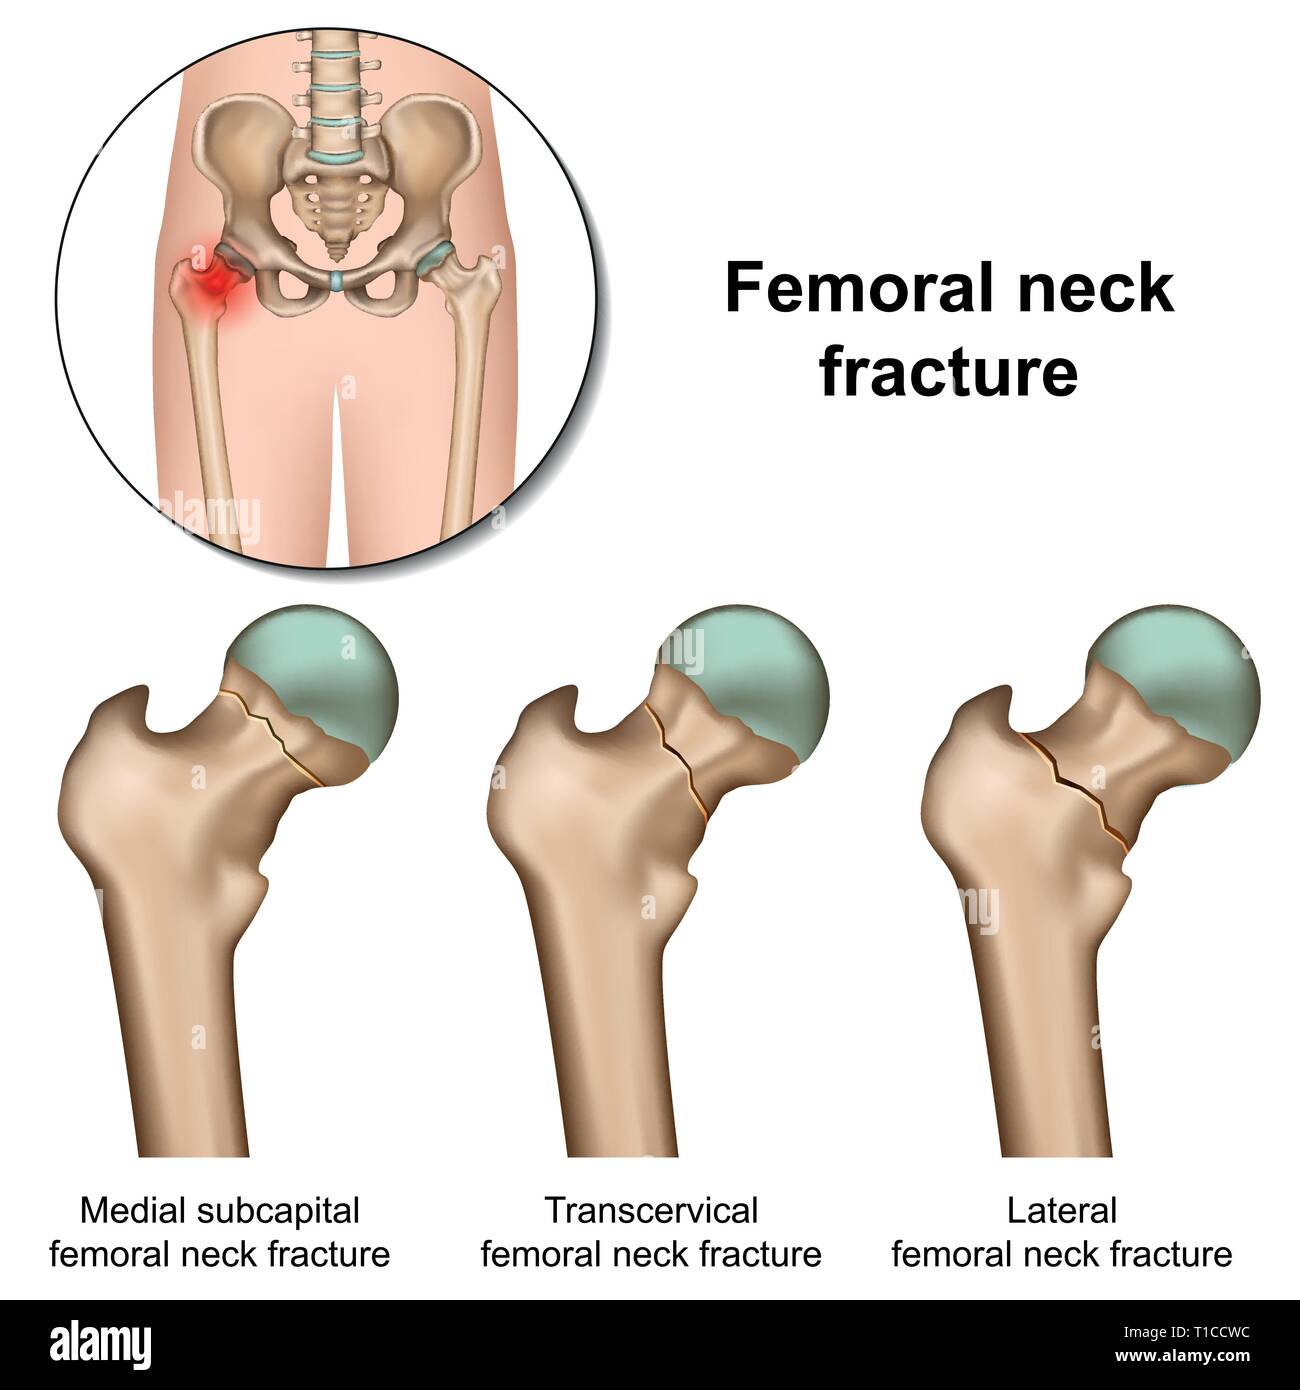

Femoral neck fractures medical vector illustration on white background Stock Vectorhttps://www.alamy.com/image-license-details/?v=1https://www.alamy.com/femoral-neck-fractures-medical-vector-illustration-on-white-background-image241833352.html

Femoral neck fractures medical vector illustration on white background Stock Vectorhttps://www.alamy.com/image-license-details/?v=1https://www.alamy.com/femoral-neck-fractures-medical-vector-illustration-on-white-background-image241833352.htmlRFT1CCWC–Femoral neck fractures medical vector illustration on white background